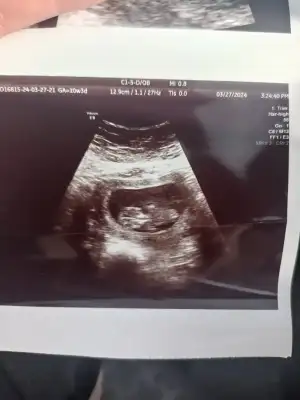

bende tahmin alabilirmiyim

Eklentiler

• 68D8609A-4D0A-487C-8CD2-FB4BED6C1B89.webp

68D8609A-4D0A-487C-8CD2-FB4BED6C1B89.webp

26,5 KB · Görüntüleme: 81

• IMG_9796.webp

IMG_9796.webp

44,4 KB · Görüntüleme: 59